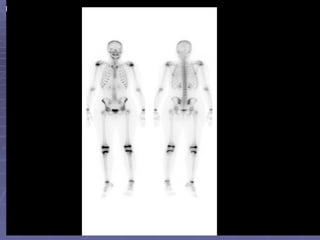

Whole body bone scan This is the bony phase of bone scan. Inject radiopharmaceutical and image in 2-4 hours. When we say bone scan, we usually mean whole body bone scan.

Whole body bonescan This is the bony phase of bone scan. Inject radiopharmaceutical and image in 2-4 hours. When we say bone scan, we usually mean whole body bone scan.

Whole Body Bone Scan